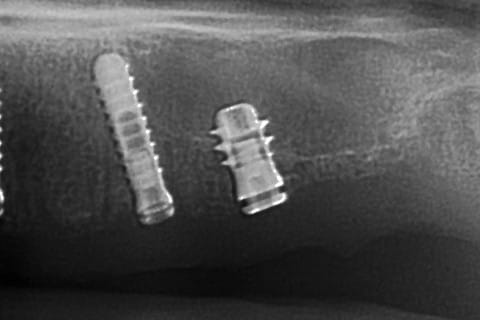

ce qui me frappe, tout de même, avec les quelques radios prises, c'est la cicatrisation osseuse au niveau de ceux en 15 et 25 (cf panos jour de la pose/3mois/4mois et les "zooms" pose/4mois)

Oups, le 2e implant en secteur 1 en partant du fond...

Celui qui est court, avec les spires distales dans le vide, enfin, il me semble...